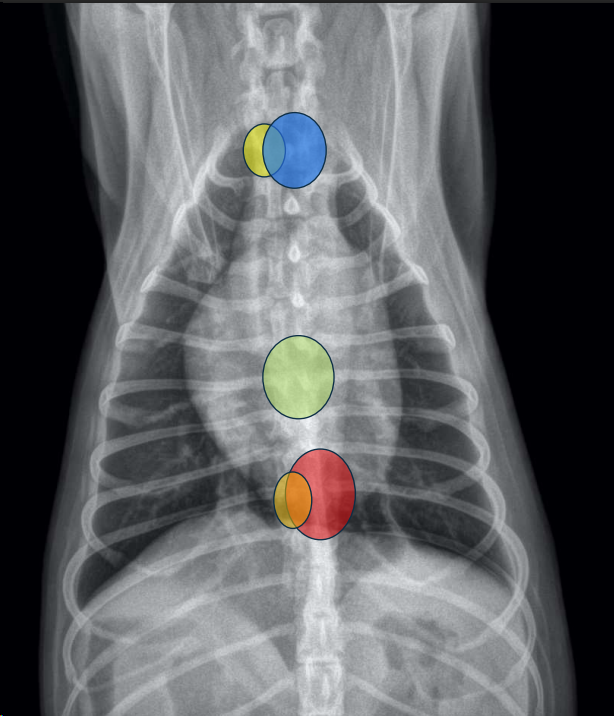

POSICIÓN DE CÁMARAS Y GRANDES VASOS (“analogía del reloj”)

Se puede comparar la silueta cardíaca con la esfera de un reloj <analogía del reloj=,utilizando los intervalos horarios para la localización de las cámaras cardíacas y de los grandes vasos.

Proyección DV:

- 11–1: arco aórtico.

- 1–2: arteria pulmonar.

- 2–3: orejuela AI.

- 3–5: ventrículo izdo.

- 5–9: ventrículo dcho.

- 9–11: aurícula dcha.